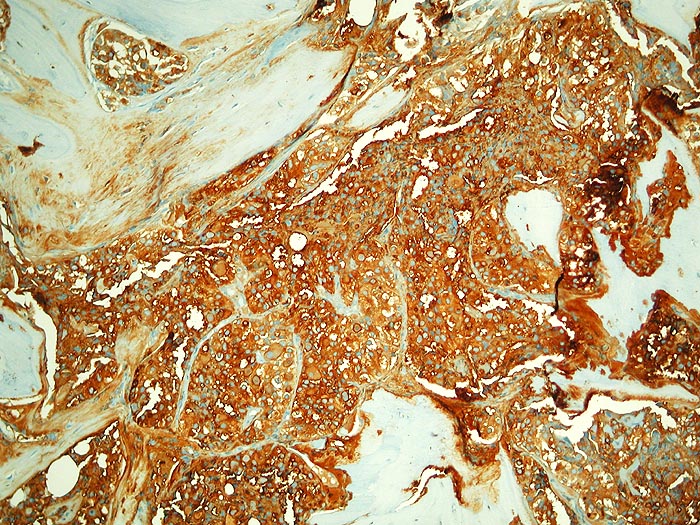

PathoPic ID 2787 - Metastase follikuläres Schilddrüsenkarzinom

Metastase follikuläres Schilddrüsenkarzinom

maligner Tumor

Knochen, Becken

Knochen, Knorpel, Gelenke

Die malignen Zellen reagieren stark mit Thyreoglobulin.

Die Tumorzellen reagieren positiv mit Thyreoglobulin sowie mit dem nukleären Transkriptionsfaktor TTF-1

Kein bekanntes Schilddrüsenkarzinom. Vor 30 Jahren Adenokarzinom des Kolons.

Histologie

Immunhistochemie

Thyreoglobulin